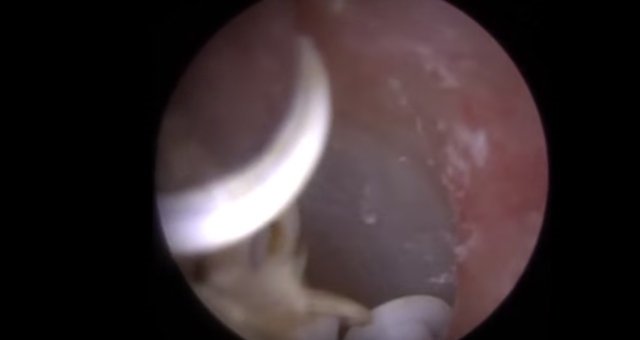

30 yıl boyunca geçmeyen bir baş ağrısı ile yaşayan bir kişi gittiği doktoru şoke etti. Yıllarca baş ağrısı çeken 59 yaşındaki adamın yaşadıkları kan dondurdu. Adamın kafasından öyle bir şey çıktı ki, doktorlar bile şaştı kaldı. İşte şoke eden olayın detayları...